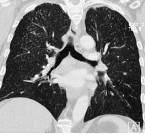

- Рентгенография органов грудной клетки. При любой патологии легочной ткани это наиболее достоверный метод диагностики. На рентгенограмме при пневмокониозе обнаруживается множество очагов диссеминации разных размеров и интенсивности, а также участки фиброзного замещения легких.

- Магнитно-резонансная и компьютерная томография. Являются дополнительными методами исследования. Позволяют визуализировать те патологические участки, которых еще не видно на рентгенограмме. Также иногда их используют для дифференциальной диагностики.

При распознавании пневмокониозов крайне важен учет профессионального маршрута пациента и наличие контактов с производственной пылью. При массовых обследованиях групп профессионального риска роль первичной диагностики пневмокониозов выполняет крупнокадровая флюорография. При этом выявляется характерное усиление и деформация легочного рисунка, наличие мелкоочаговых теней.

Углубленное обследование (рентгенография легких, компьютерная томография, МРТ легких) позволяет уточнить характер пневмокониоза (интерстициальный, узелковый и узловой) и стадию изменений. При прогрессировании пневмокониоза увеличивается площадь поражения, размеры и количество теней, выявляются участки массивного фиброза, компенсаторная эмфизема, утолщение и деформация плевры и т. д. Оценка кровотока и вентиляции в различных участках легочной ткани проводится с помощью зональной реопульмонографии и сцинтиграфии легких.

Основным диагностическим методом определения пневмокониоза является рентгенологическое исследование.